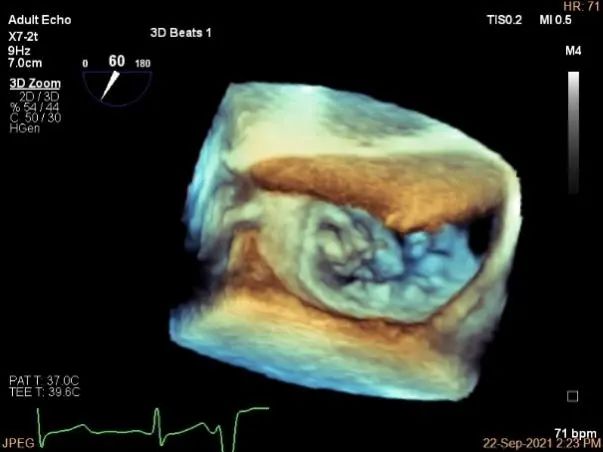

术中超声

3D:P1区脱垂并腱索断裂,部分AC受累,Width:11.4mm

3D调orientation

3d确认夹子位置在P1区